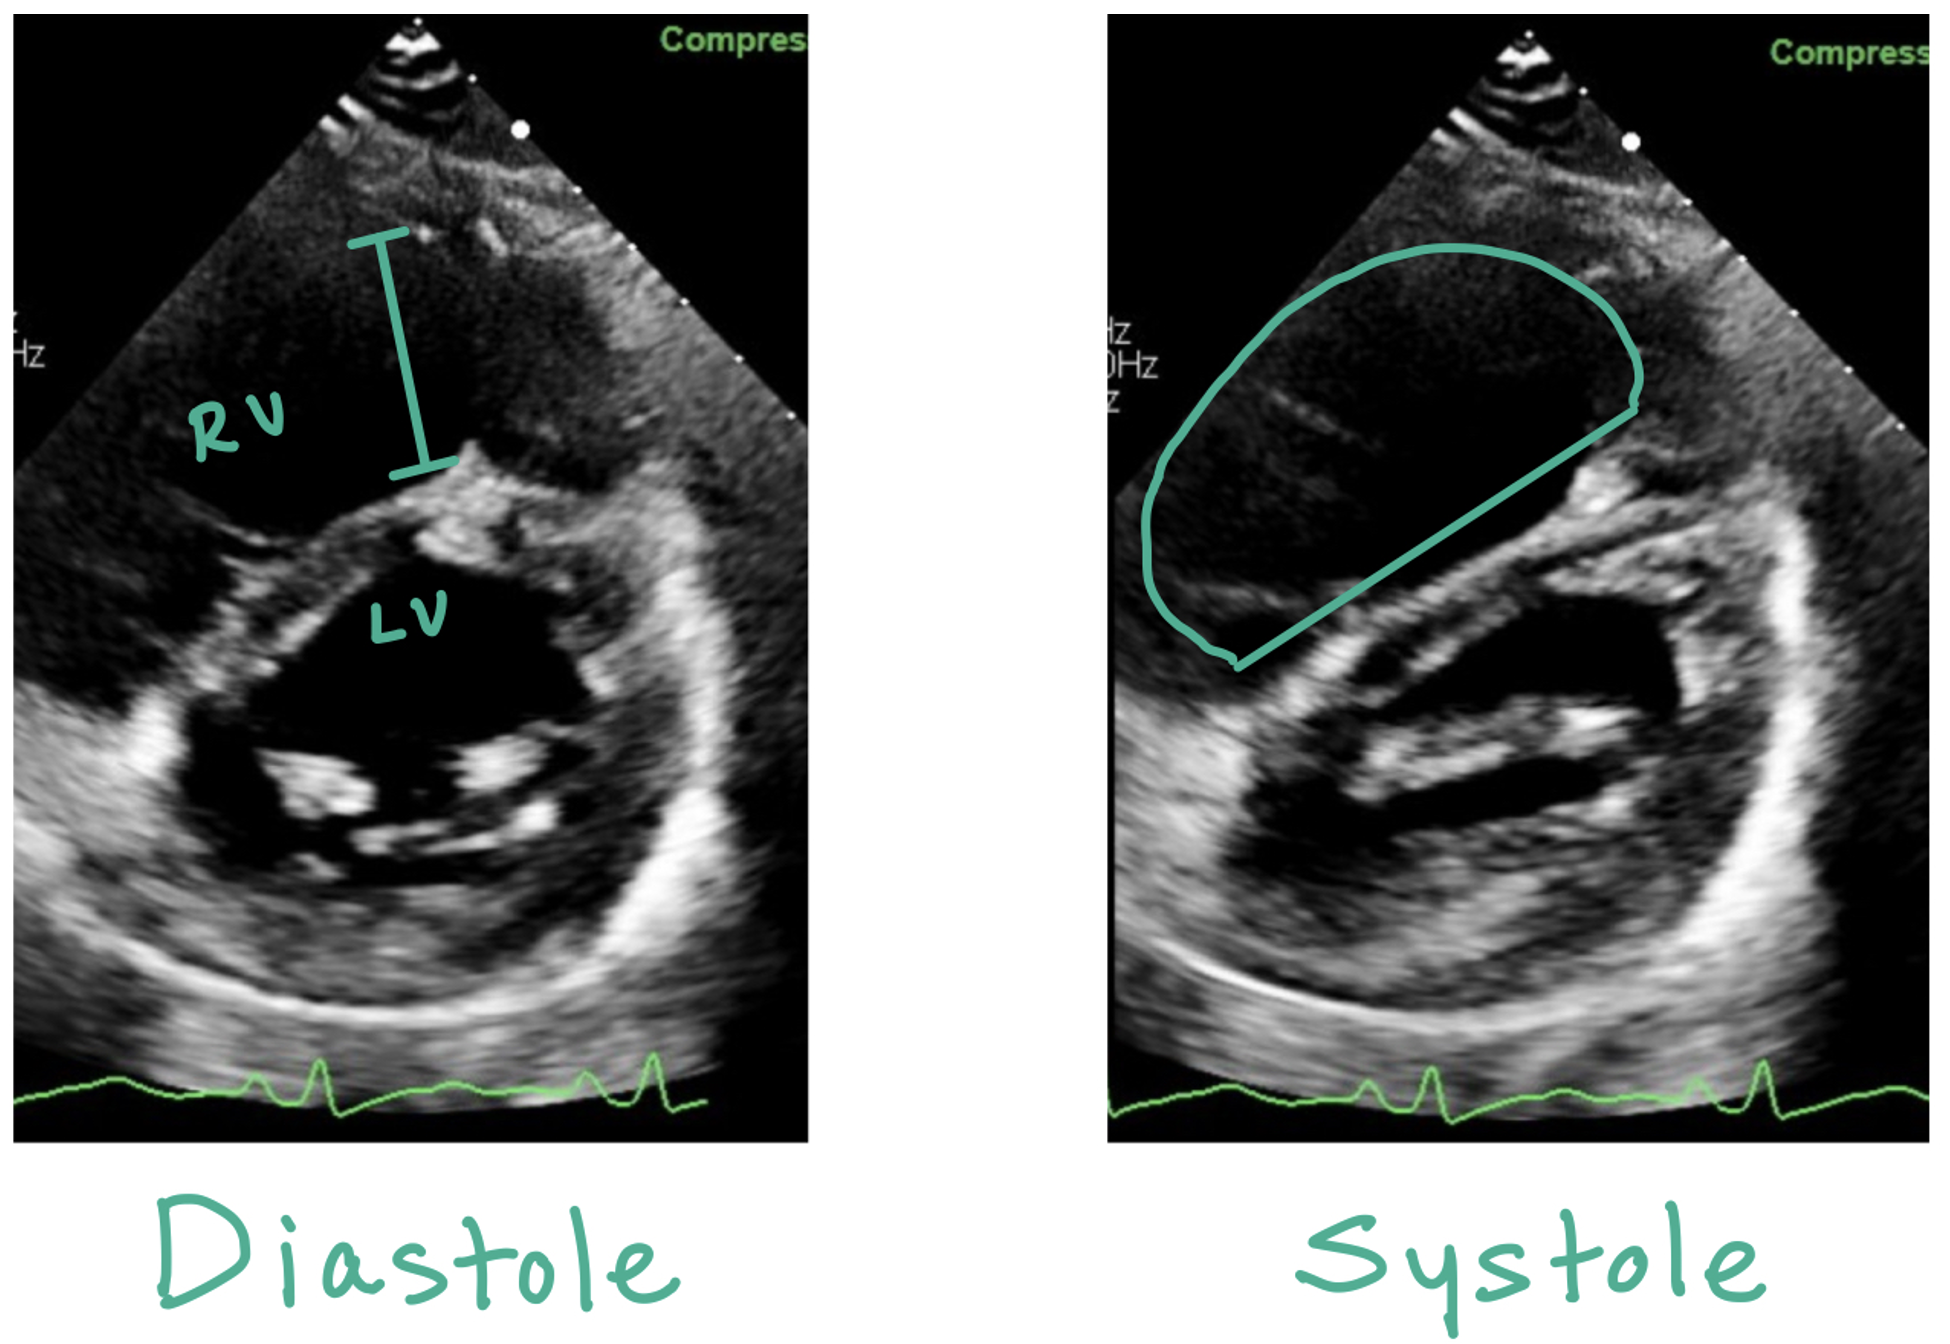

This picture compares the parasternal short views in a normal heart vs a heart with increased RV strain. D Sign occurs when there is RV pressure overload; in the parasternal short view, the LV should normally appear round in diastole and systolic. When there is pressure overload, the LV will appear D shaped throughout the cardiac cycle.

The picture on the left is an apical four chamber view of a normal heart. The picture on the right depicts a heart with a PE. Note the right ventricular (RV) enlargement, hyperkinetic apex, and hypokinetic right ventricle. McConnell’s sign occurs when there is relative hyperkinesis of the RV apex compared to the RV free wall (occurs as the LV apex is hyperkinetic and tethered to the RV apex, causing it to appear hyperkinetic)